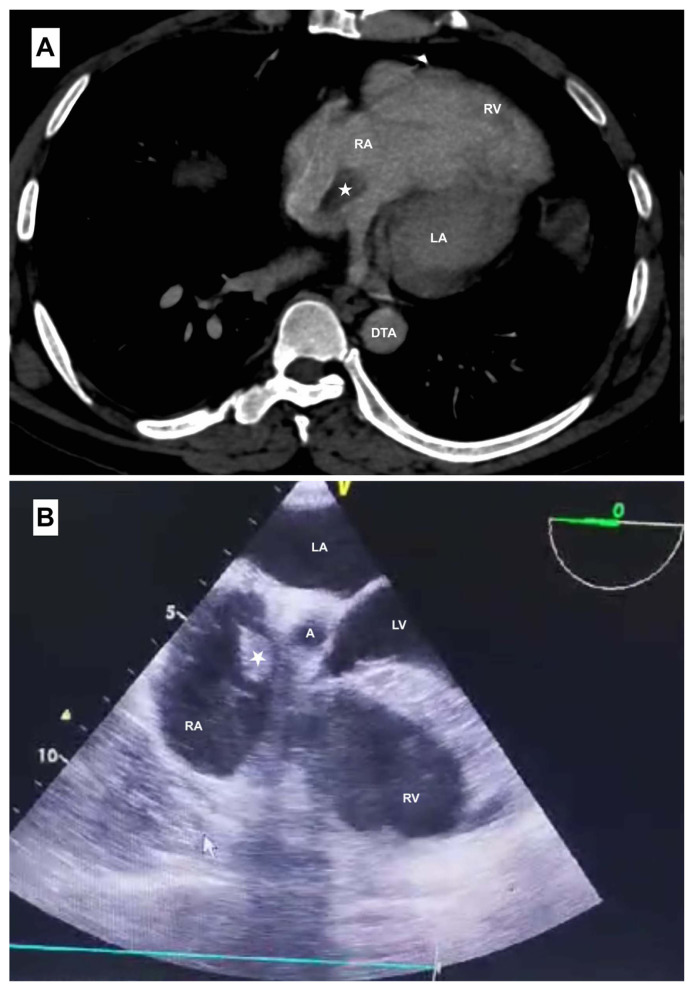

Atrial septal defects are among the most prevalent congenital anomalies necessitating surgical intervention. Thrombus formation is a recognized complication that is typically characterized by an embolic event following patch-based repair. However, thromboembolic complications following primary repair of atrial septal defects are exceedingly uncommon. Minimally invasive surgery is a suitable alternative to redo sternotomy. We present a 46-year-old man who was diagnosed with a right atrial mass eight years following the patch repair of an atrial septal defect and underwent a successful minimally invasive redo surgery.

Abstract Image